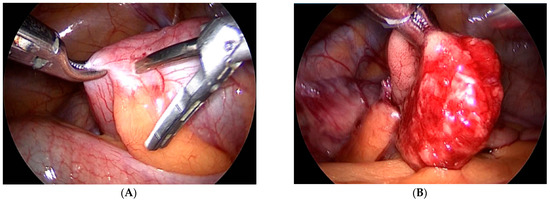

The seventh case in our case series is a 6-year-old boy who was referred to our clinic for a suspected ileocecal invagination. A hydrostatic desinvagination guided by ultrasound was attempted, and a patent ileocecal valve was confirmed. A pseudo kidney formation remained, indicating the possibility of an invagination of the duodenum and small intestine. A repeated ultrasound demonstrated that a pseudo-invagination was still present in the upper left quadrant. An MR-enterography was performed and demonstrated a 20-centimeter long suspected intussusception in the left hemiabdomen beginning in the third part of the duodenum and continued below the ligament of Treitz. Multiple polyps of the duodenum and jejunum were suggestive of Peutz–Jeghers syndrome as well. The most proximal polyp with a diameter of 6 cm produced a marked narrowing of the distal part of the duodenum and proximal jejunum. An esophago-gastro-duodenoscopy was performed, and a biopsy was taken. The biopsy confirmed the presence of a hyperplastic polyp of the duodenum. Then, the duodenum and jejunum were exposed using a combined laparoscopic–endoscopic “rendezvous” procedure (Figure 3A). A vertical incision was made on the highest position of the jejunal wall, and the mucosa was mobilized. However, the polyp could not be visualized during the first attempt. Then, we decided to use a partial Cattell–Braasch maneuver and resection of the ligament of Treitz for better mobilization of the duodenal mucosa (Figure 3B). After the resection of the ligament, the natural curvature of the duodeno-jejunal flexure was straightened. The straightened duodeno-jejunal junction allowed for the visualization and resection of the duodenal polyp (Figure 4). A second enterotomy was performed distally on the jejunum as well and two more polyps were resected (diameter 20 and 15 mm, respectively). The histology confirmed Peutz–Jeghers syndrome.

Figure 3. (A) Endoscopic navigation by transillumination of the duodenum and jejunum, (B) Cattell–Braasch maneuver.

Figure 4. Laparoscopic excision of the duodenal polyp (The straightened duodeno-jejunal junction allowed for the visualization and resection of the duodenal polyp during repeated mucosal mobilization).

For decades after minimally invasive laparoscopic surgery has been introduced, duodenal lesions were impossible to resect using this approach. Recently, more and more surgeons are attempting to extend their field of work to the duodenum and endoscopic guidance can be of tremendous help during this procedure. Here, we reported a case of a duodenal polyp treated in this way. The Cattell–Braasch maneuver and resection of the ligament of Treitz were used in order to straighten the natural duodeno-jejunal flexure. In 1960, Cattel and Braasch described the technique for the mobilization of the third and fourth portion of the duodenum that is used until today [16]. This maneuver consists of dissection of the line of Toldt from the common bile duct until the ligament of Treitz. Additional mobilization of the suspensory muscle of the duodenum (ligament of Treitz) was performed in the case we report here for complete mobilization of the duodenum. After the resection of the ligament, the natural curvature of the duodeno-jejunal flexure was straightened. The straightened duodeno-jejunal junction allowed for the visualization and resection of the duodenal polyp during repeated mucosal mobilization. Nowadays, laparoscopic endoscopic cooperative surgery, combining endoscopic submucosal dissection and laparoscopic seromuscular incision, is reported to be successful in treating duodenal lesions as well [17].